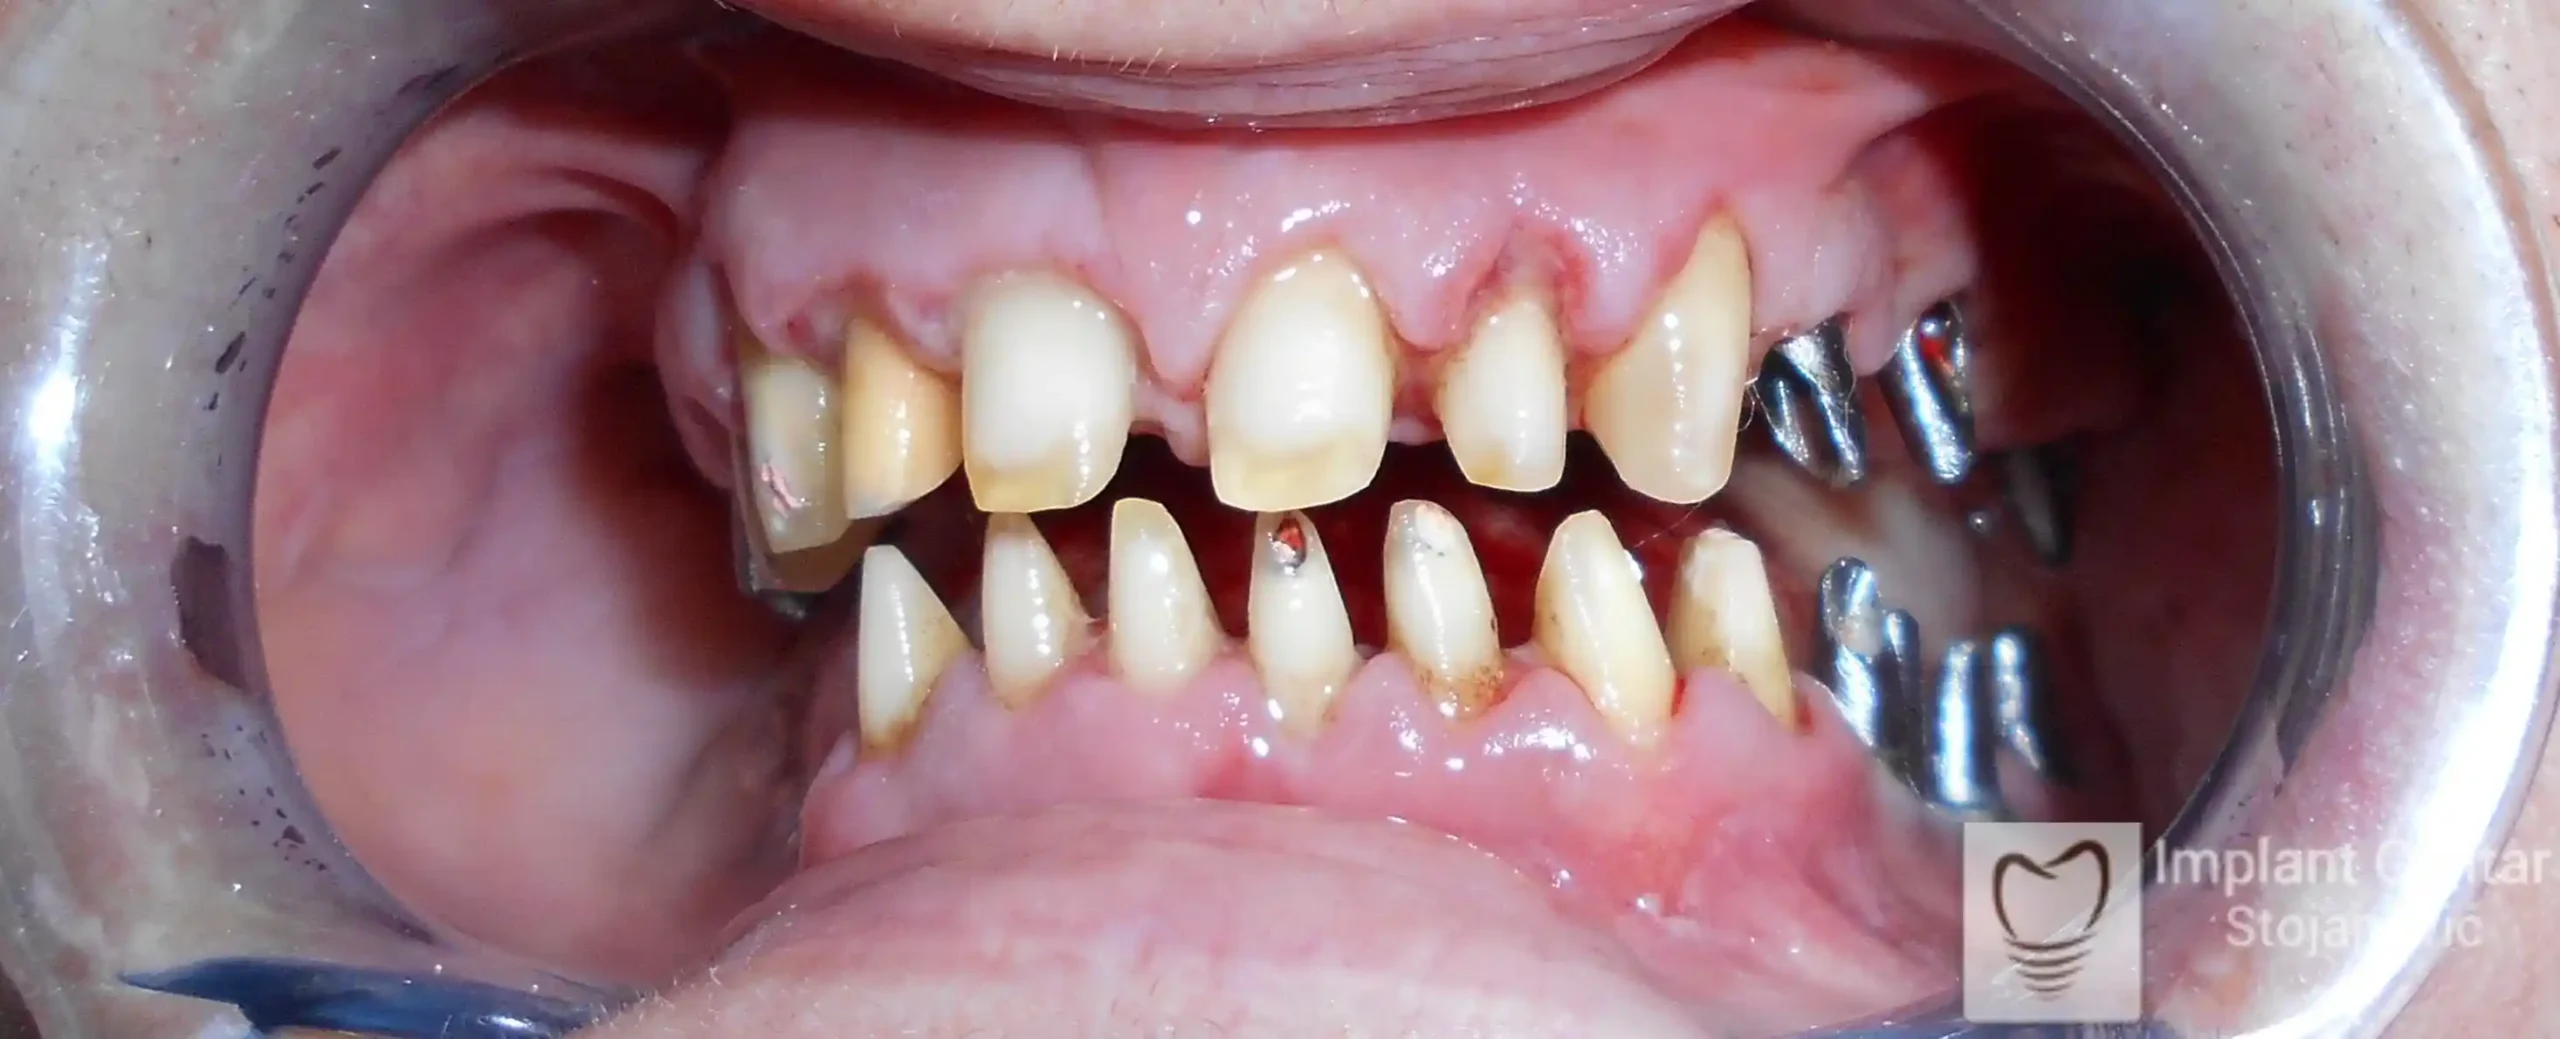

Na slikama 1, 2, 3 , 4  i  5 prikazan je izgled pacijenta pre početka terapije. Nakon detaljne kliničke i radiološke analize, doneta je odluka o vađenju zuba loše biološke vrednosti, dok su bezuba polja sanirana ugradnjom dentalnih implantata.

Nakon ugradnje implantata i pripreme preostalih zuba, pacijentu su izrađene fiksne privremene krunice, čime je postignut eugnatan zagriz već nakon jednog dana (slika 8, 9 i 10). Tokom perioda osteointegracije, pacijent se postepeno privikavao na novi položaj vilica i zagriz.